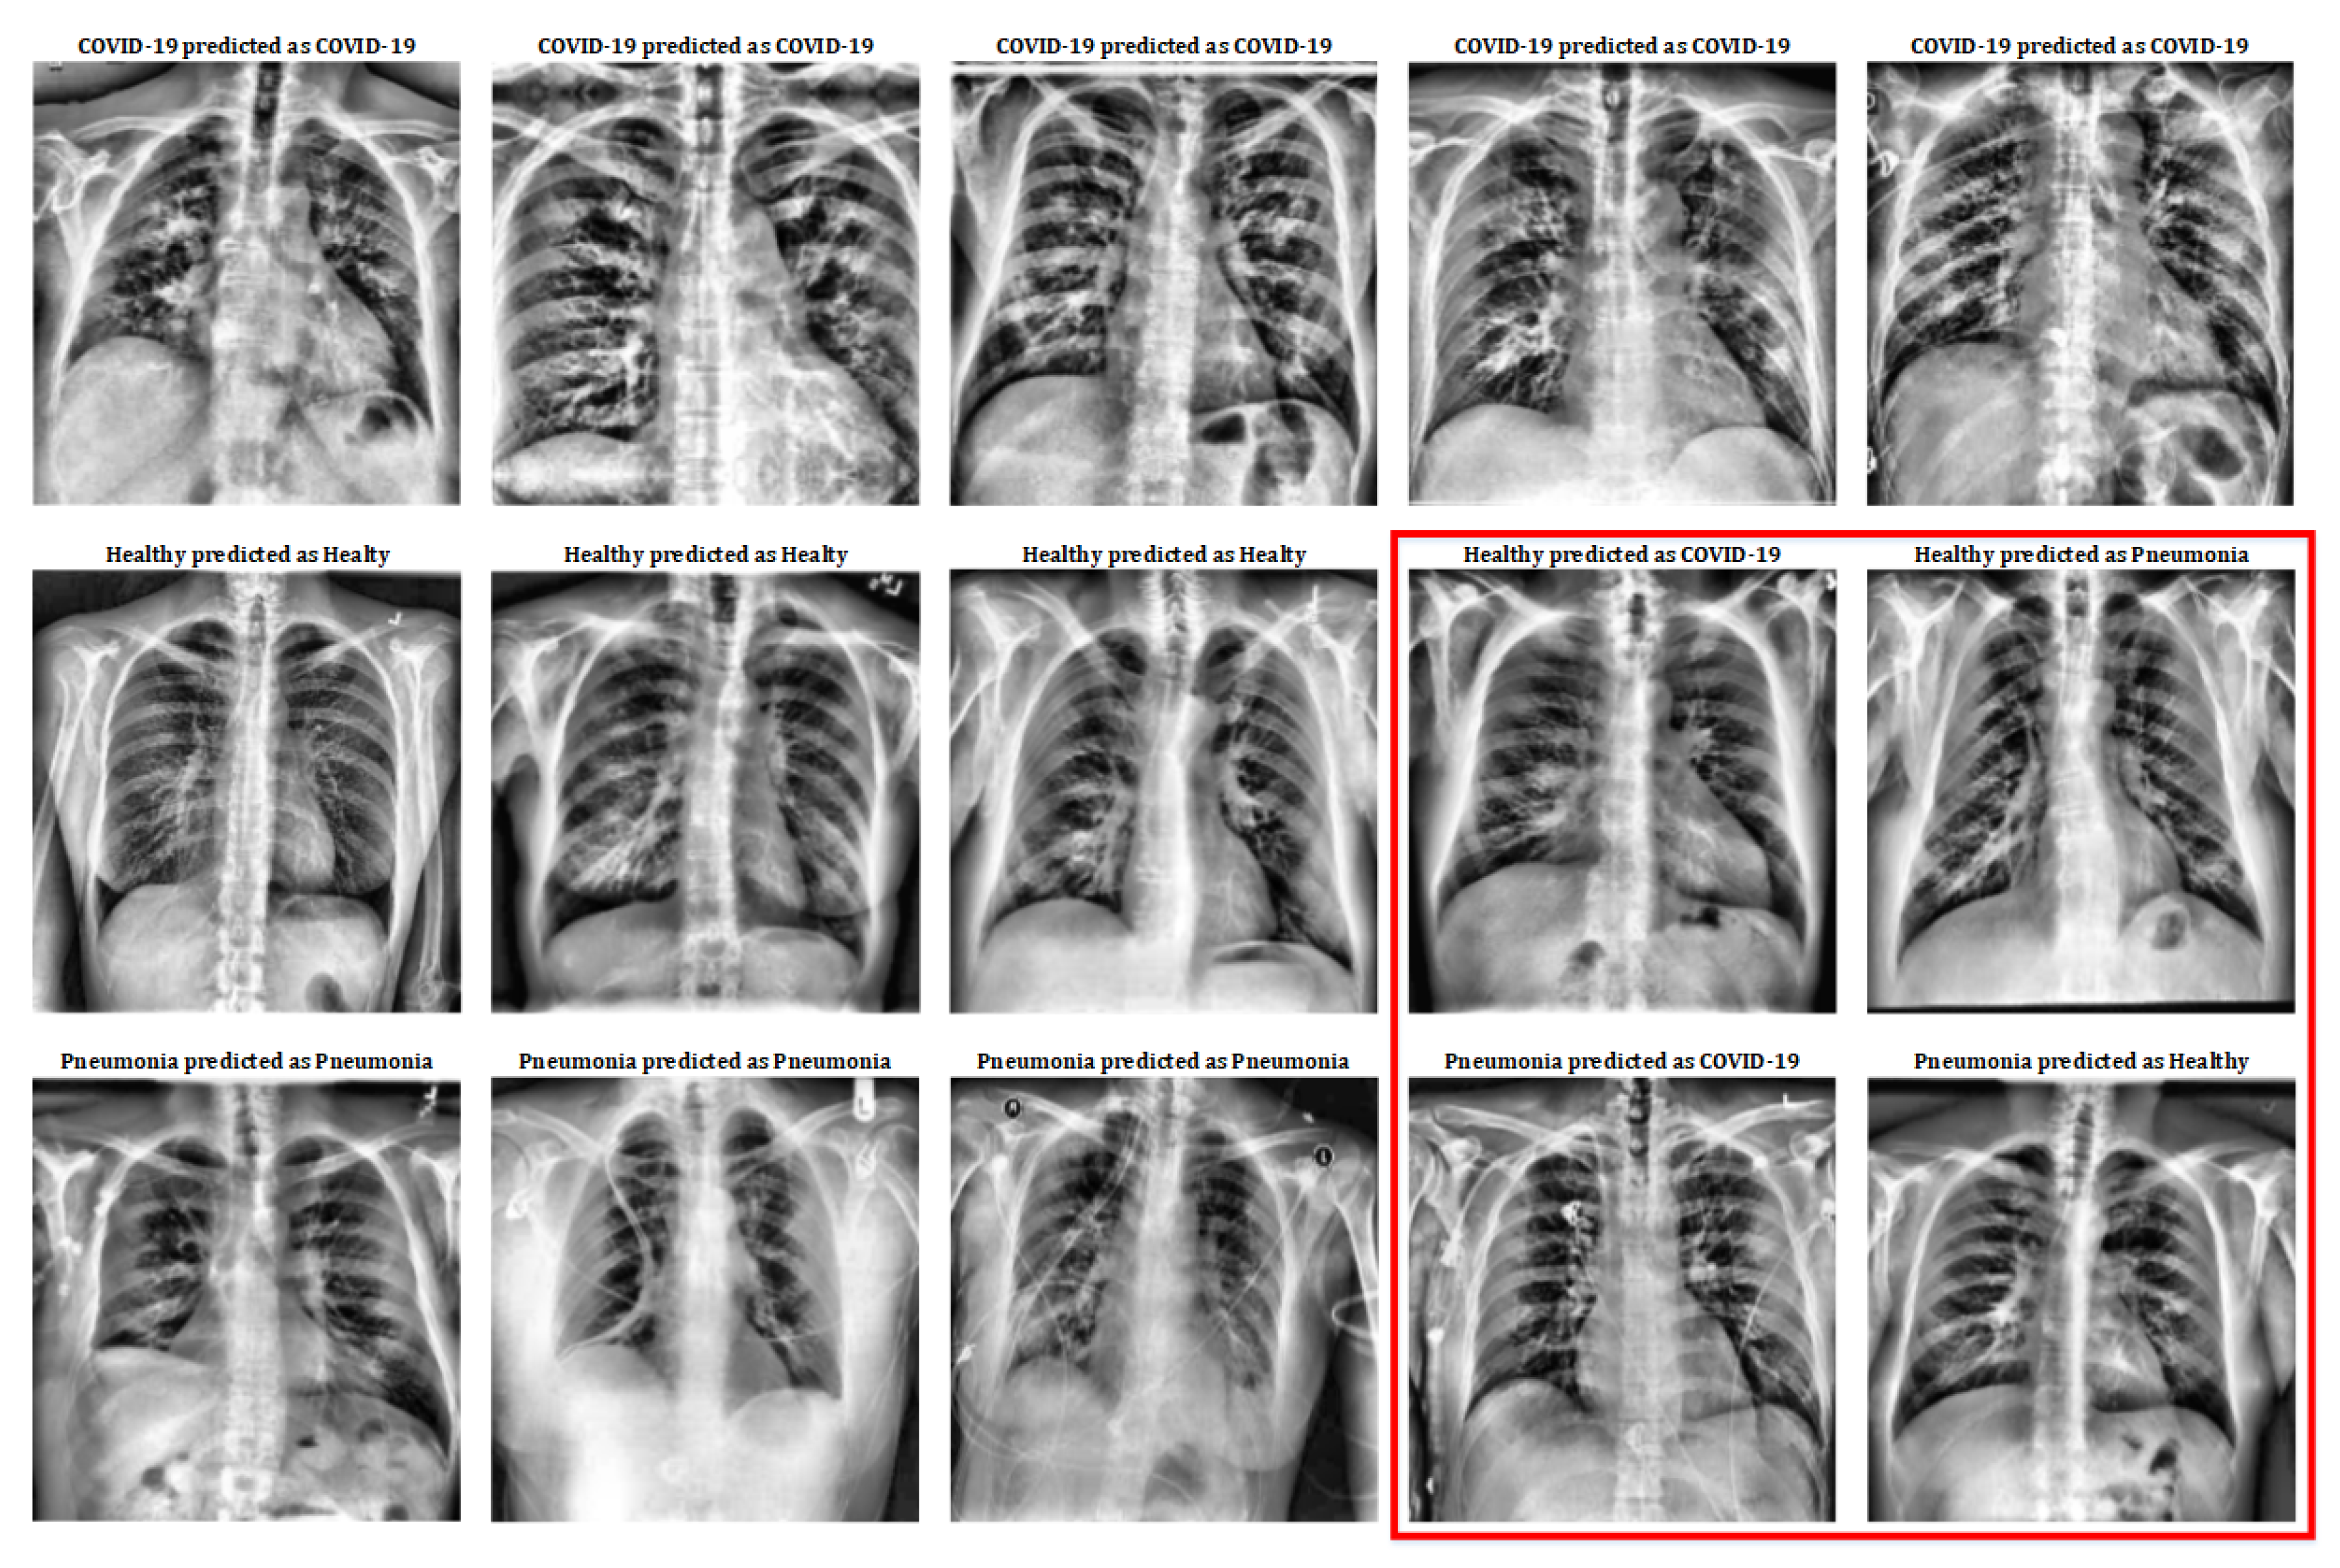

In this section we present the methodology for COVID-19 detection by means of a chest X-ray image.

Some people have pneumonia a lung infection in which the alveoli are inflamed. Imaging the coronavirus disease COVID-19 Chest X-ray is the first imaging method to diagnose COVID-19 coronavirus infection in Spain but in the light of new evidence this may change soon according to Milagros Martí de Gracia Vice President of the Spanish Society of Radiology SERAM and head of the emergency radiology unit at La Paz Hospital in Madrid one of the hot spots for viral re-production of. 2020 our baseline methodAlso we describe the employed deep learning techniques as well as the learning methodology and evaluation.

We detail the main datasets and briefly describe the COVID-Net Wang et al. Under these recommendations X-ray examinations can be considered if a child suspected with COVID-19 has moderate to severe symptoms of acute respiratory disease. If you have a patient you think was exposed to COVID and has typical symptoms then a.